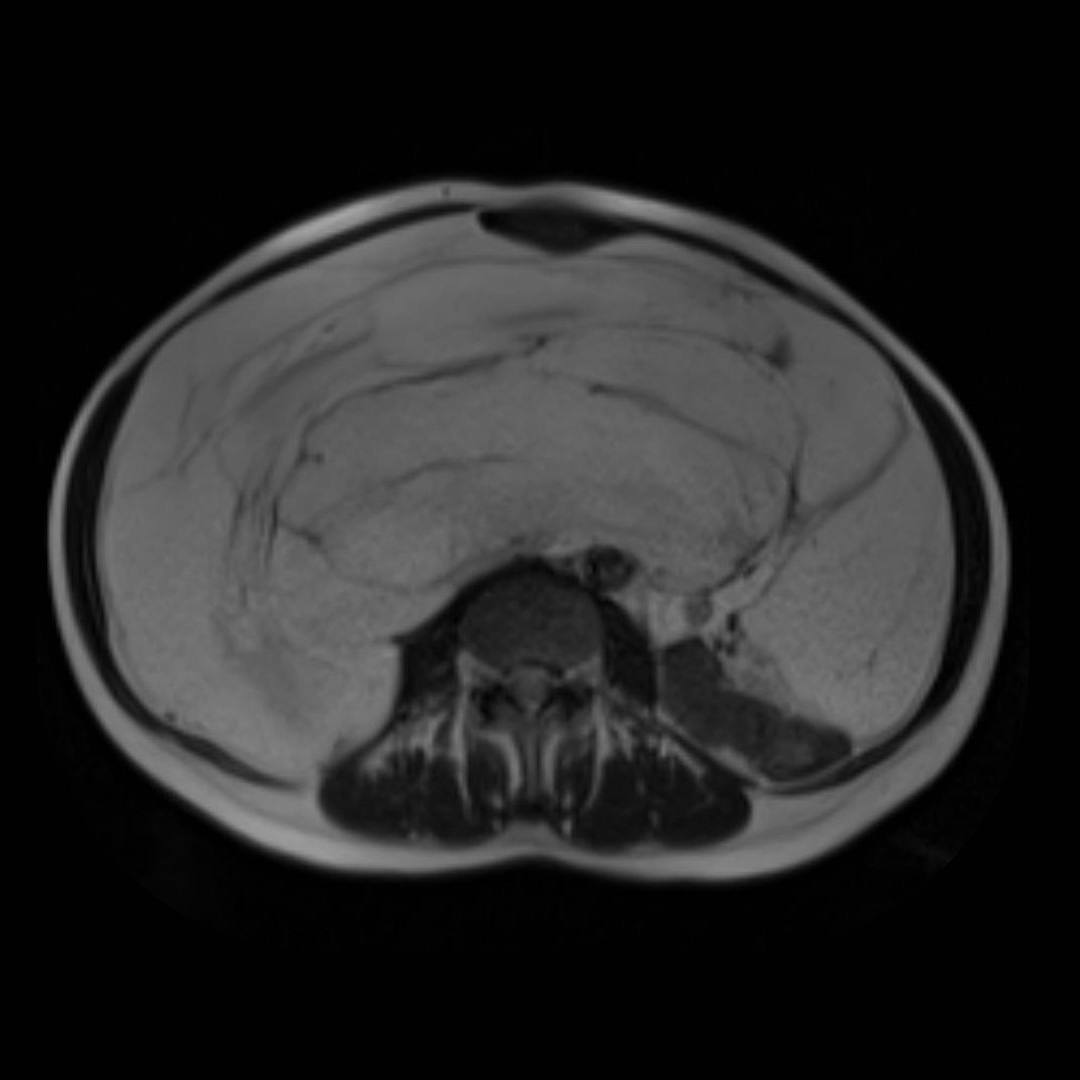

С целью оценки образования, а также уточнения расположения и взаимоотношения с органами брюшной полости проведено МРТ органов брюшной полости с внутривенным контрастированием.

При МРТ было выявлено жиросодержащее внеорганное объемное образование больших размеров с множественными неравномерными накапливающими контрастный препарат перегородками, занимающее большую часть брюшной полости с признаками смещения прилежащих внутренних органов.

Учитывая особенности структуры образования, распространенность и расположение, находка расценена как липосаркома (злокачественная опухоль жировой ткани).